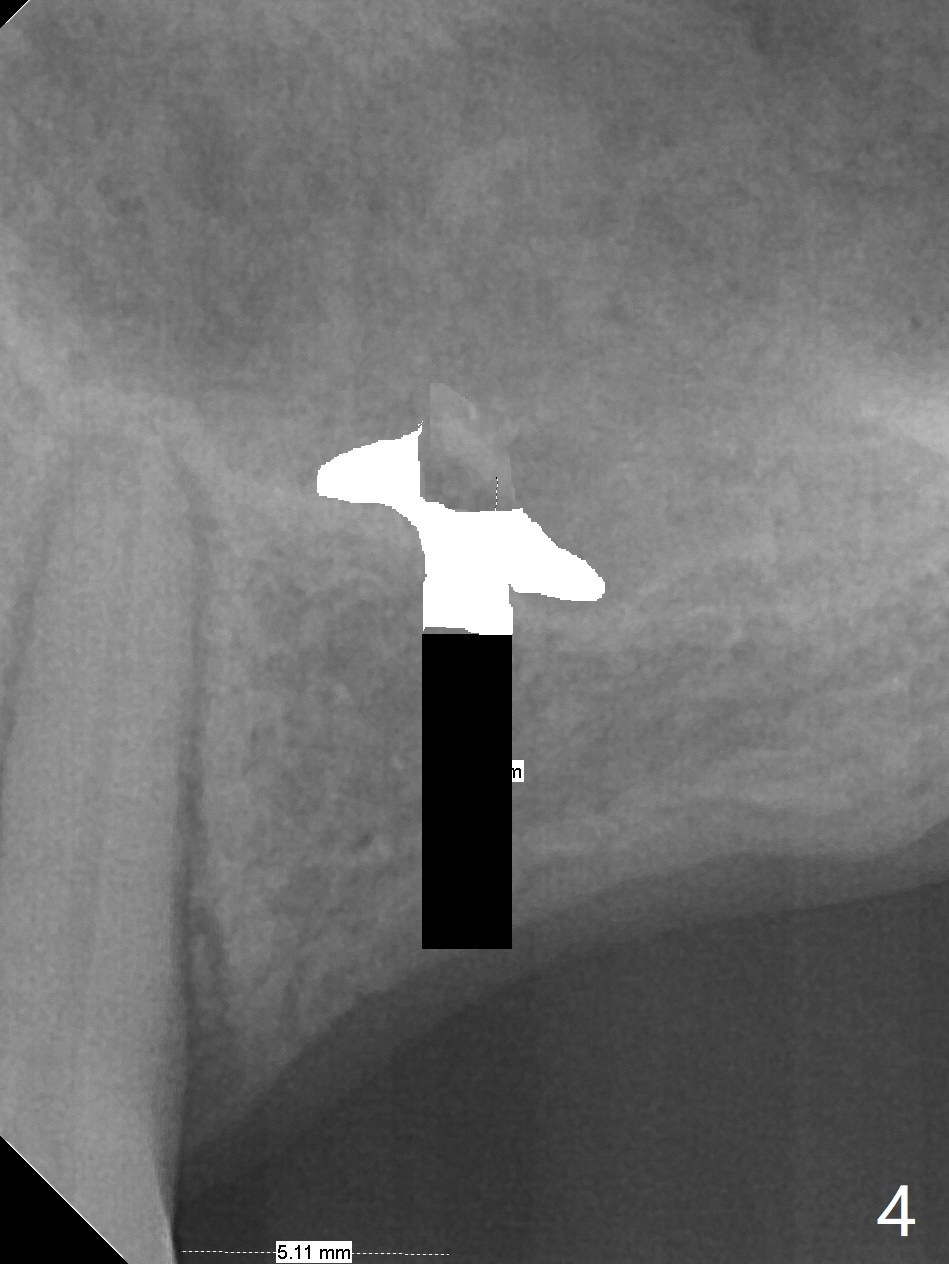

A 57-year-old woman has lost #14,15 and 18 for a while (Fig.1). Because of fear, an implant will be placed at #14 first (Fig.2). After use of Magic Drill for 5 mm (Fig.3), Magic Lifter will be used for lift (Fig.4). Following placement of PRF membrane (Fig.5 blue) and Vanilla Graft (red circles), a dummy implant is placed for additional lift (Fig.6 green). With placement of a larger and probably longer definitive implant, the graft may migrate distal due to gravity in sleep (Fig.7 arrow). In a few months, the bone height at #15 may increase to facilitate implant placement at #15.